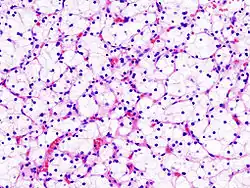

| Micrograph of the most common type of renal cell carcinoma (clear cell)—on right of the image; non-tumour kidney is on the left of the image. Nephrectomy specimen. H&E stain | |

The gross and microscopic appearance of renal cell carcinomas is highly variable. The renal cell carcinoma may present reddened areas where blood vessels have bled, and cysts containing watery fluids.[64] The body of the tumour shows large blood vessels that have walls composed of cancerous cells. Gross examination often shows a yellowish, multilobulated tumor in the renal cortex, which frequently contains zones of necrosis, haemorrhage and scarring. In a microscopic context, there are four major histologic subtypes of renal cell cancer: clear cell (conventional RCC, 75%), papillary (15%), chromophobic (5%), and collecting duct (2%). Sarcomatoid changes (morphology and patterns of IHC that mimic sarcoma, spindle cells) can be observed within any RCC subtype and are associated with more aggressive clinical course and worse prognosis. Under light microscopy, these tumour cells can exhibit papillae, tubules or nests, and are quite large, atypical, and polygonal.

Recent studies have brought attention to the close association of the type of cancerous cells to the aggressiveness of the condition. Some studies suggest that these cancerous cells accumulate glycogen and lipids, their cytoplasm appear "clear", the nuclei remain in the middle of the cells, and the cellular membrane is evident.[65] Some cells may be smaller, with eosinophilic cytoplasm, resembling normal tubular cells. The stroma is reduced, but well vascularised. The tumour compresses the surrounding parenchyma, producing a pseudocapsule.[66]

The most common cell type exhibited by renal cell carcinoma is the clear cell, which is named by the dissolving of the cells' high lipid content in the cytoplasm. The clear cells are thought to be the least likely to spread and usually respond more favourably to treatment. However, most of the tumours contain a mixture of cells. The most aggressive stage of renal cancer is believed to be the one in which the tumour is mixed, containing both clear and granular cells.[67]

The recommended histologic grading schema for RCC is the Fuhrman system (1982), which is an assessment based on the microscopic morphology of a neoplasm with haematoxylin and eosin (H&E staining). This system categorises renal cell carcinoma with grades 1, 2, 3, 4 based on nuclear characteristics. The details of the Fuhrman grading system for RCC are shown below:[68]